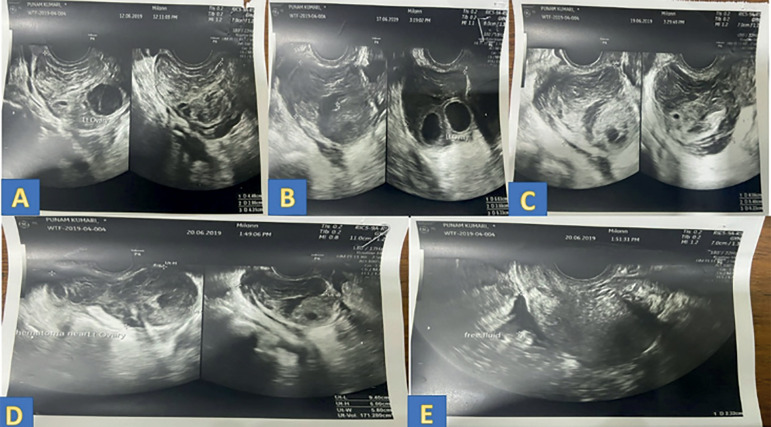

Management of peri-ovarian hematoma following oocyte retrieval in a pooling cycle IVF: Case report.

Here we report a case of peri-ovarian hematoma following ovum pick-up in a patient in a pooling cycle IVF (in vitro fertilization). We have attempted to discuss the possible mechanisms for the development of hematoma in such patients, the common clinical presentation, monitoring, and management of these cases. The decision to operate or to manage conservatively forms an important aspect of managing such patients. This case report can help to keep the clinicians alert while managing this subgroup of patients.